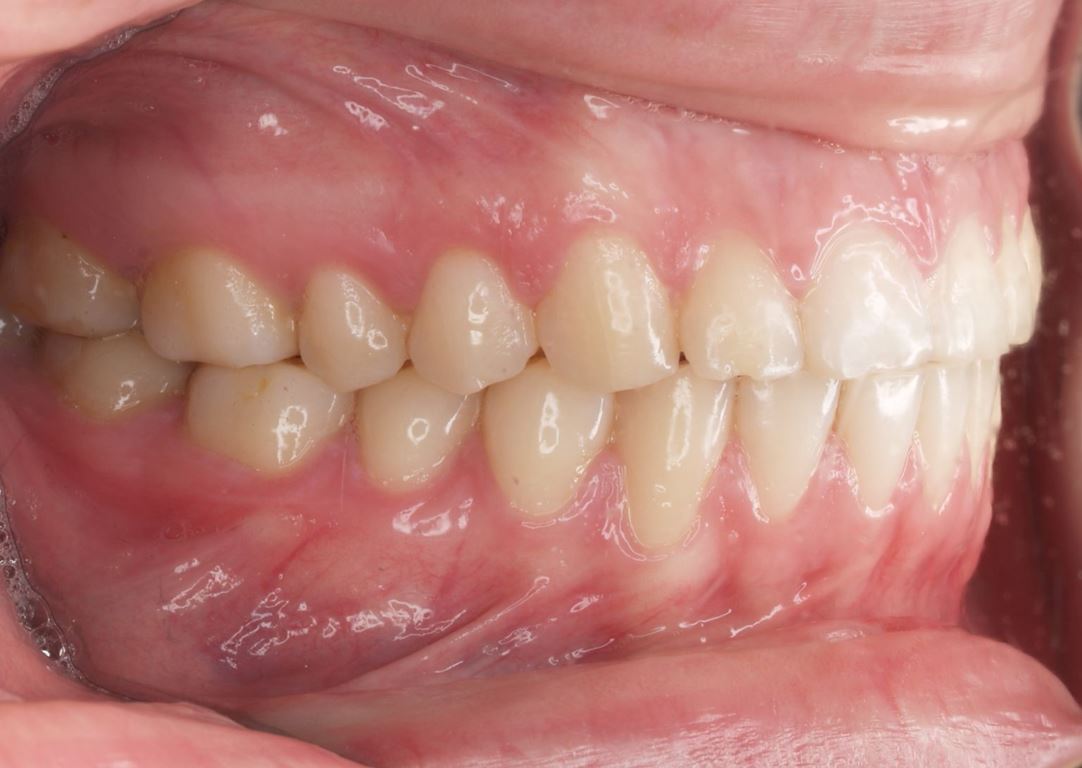

W pierwszym etapie diagnostycznym wykonano zdjęcia zewnątrz- i wewnątrzustne (ryc. 1-12).

Bezpośrednio po usunięciu zębów rozpoczęto leczenie ortodontyczne, które trwało 15 miesięcy i pozwoliło na uzyskanie zaplanowanych wcześniej pozycji zębów (ryc. 22-24).